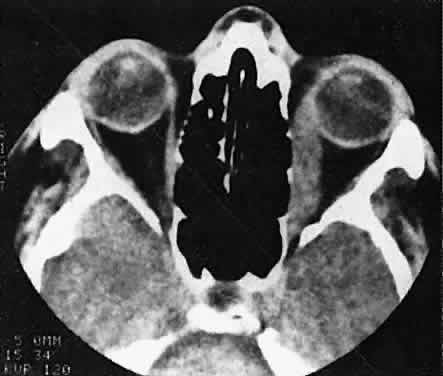

Orbital myositis may represent a greater proportion of cases of IIPT in childhood than in adulthood, and involvement of multiple extraocular muscles may occur more frequently in children than inadults. In orbital myositis, early diplopia and increased discomfort with attempted eye movement are typical symptoms. CT may show enlargement of one or more extraocular muscles in one or both orbits (Figs. 21 and 22). When a single muscle is involved, the specter of a primary or metastatic neoplasm within the muscle may be raised. However, external inflammatory signs, considerable pain and limited motility, and an explosive onset of symptoms within 24 hours all suggest orbital myositis. The uniform enlargement of the muscle, including its tendinous insertion (see Fig. 22), also helps distinguish the process from a neoplasm, which might be expected to produce a more focal, globular expansion. Echography may support the diagnosis of inflammation by showing edema in the episcleral space as a relative sonolucency between the scleral and orbital fat echoes (Fig. 23). Its CT counterpart is an increase in the radiodensity and thickness of the ocular tunica.

Fig. 22. The uniform enlargement of the left medial rectus muscle, including its tendinous insertion, is characteristic of orbital myositis.